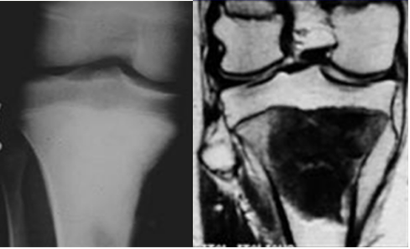

Fig 19. Lesión diafisiaria.

Rx AP. Imagen compatible con encondroma, en la diafisis tibial.